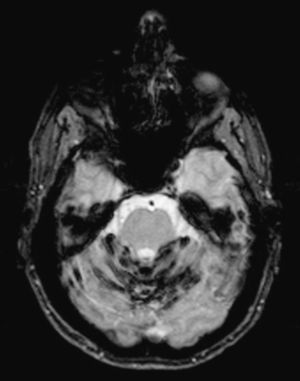

La RM medular mostró cambios quirúrgicos dorsales con resección de elementos posteriores y un voluminoso seudomeningocele posterolateral izquierdo en T4-T5, zona de la intervención del tumor, que desplazaba el cordón medular y remodelaba las estructuras vertebrales adyacentes. No se observaron alteraciones significativas en la señal de resonancia medular, a excepción de un fino halo hipointenso periférico en secuencias GE a nivel de la intervención, que probablemente correspondía también a una mínima siderosis meníngea (fig. 2).